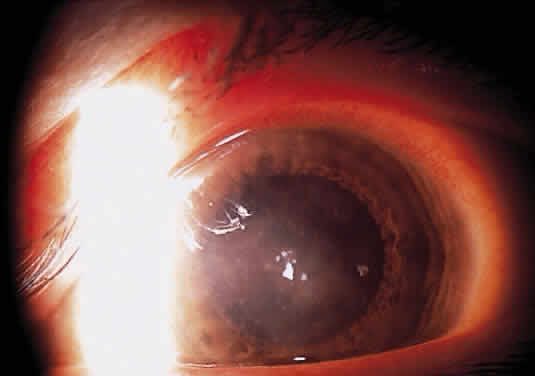

Herpetic keratouveitis can occur in association with any form of herpetic keratitis. Anterior chamber inflammation that accompanies epithelial disease is thought to be caused by reflex irritation and is characteristically both mild and transient. However, the iridocyclitis that invariably accompanies necrotizing disease tends to be much more severe, and is not necessarily correlated with the apparent severity of the keratitis. Indeed, although uveitis dominates the clinical picture in some cases of ocular HSV, subtle corneal findings are limited to faint cellular infiltration of the stroma. Uveitis that accompanies necrotizing disease is typically granulomatous and often recurrent. In more severe cases, perilimbal injection is marked, and the cornea can become thickened and edematous. Dense, fibrinous flare with heavy, anterior chamber cell and medium-sized white keratic precipitates may be distributed widely over the endothelium (Fig. 2). A hypopyon and synechiae can form, and elevated intraocular pressure that exacerbates this often painful uveitis may develop. Marked dilation of iris blood vessels and spontaneous hyphemas sometimes occur. Episodes of inflammation are frequently marked by progressive iris atrophy and sphincter damage, leading to corectopia and anisocoria (Figs. 3 and 4).